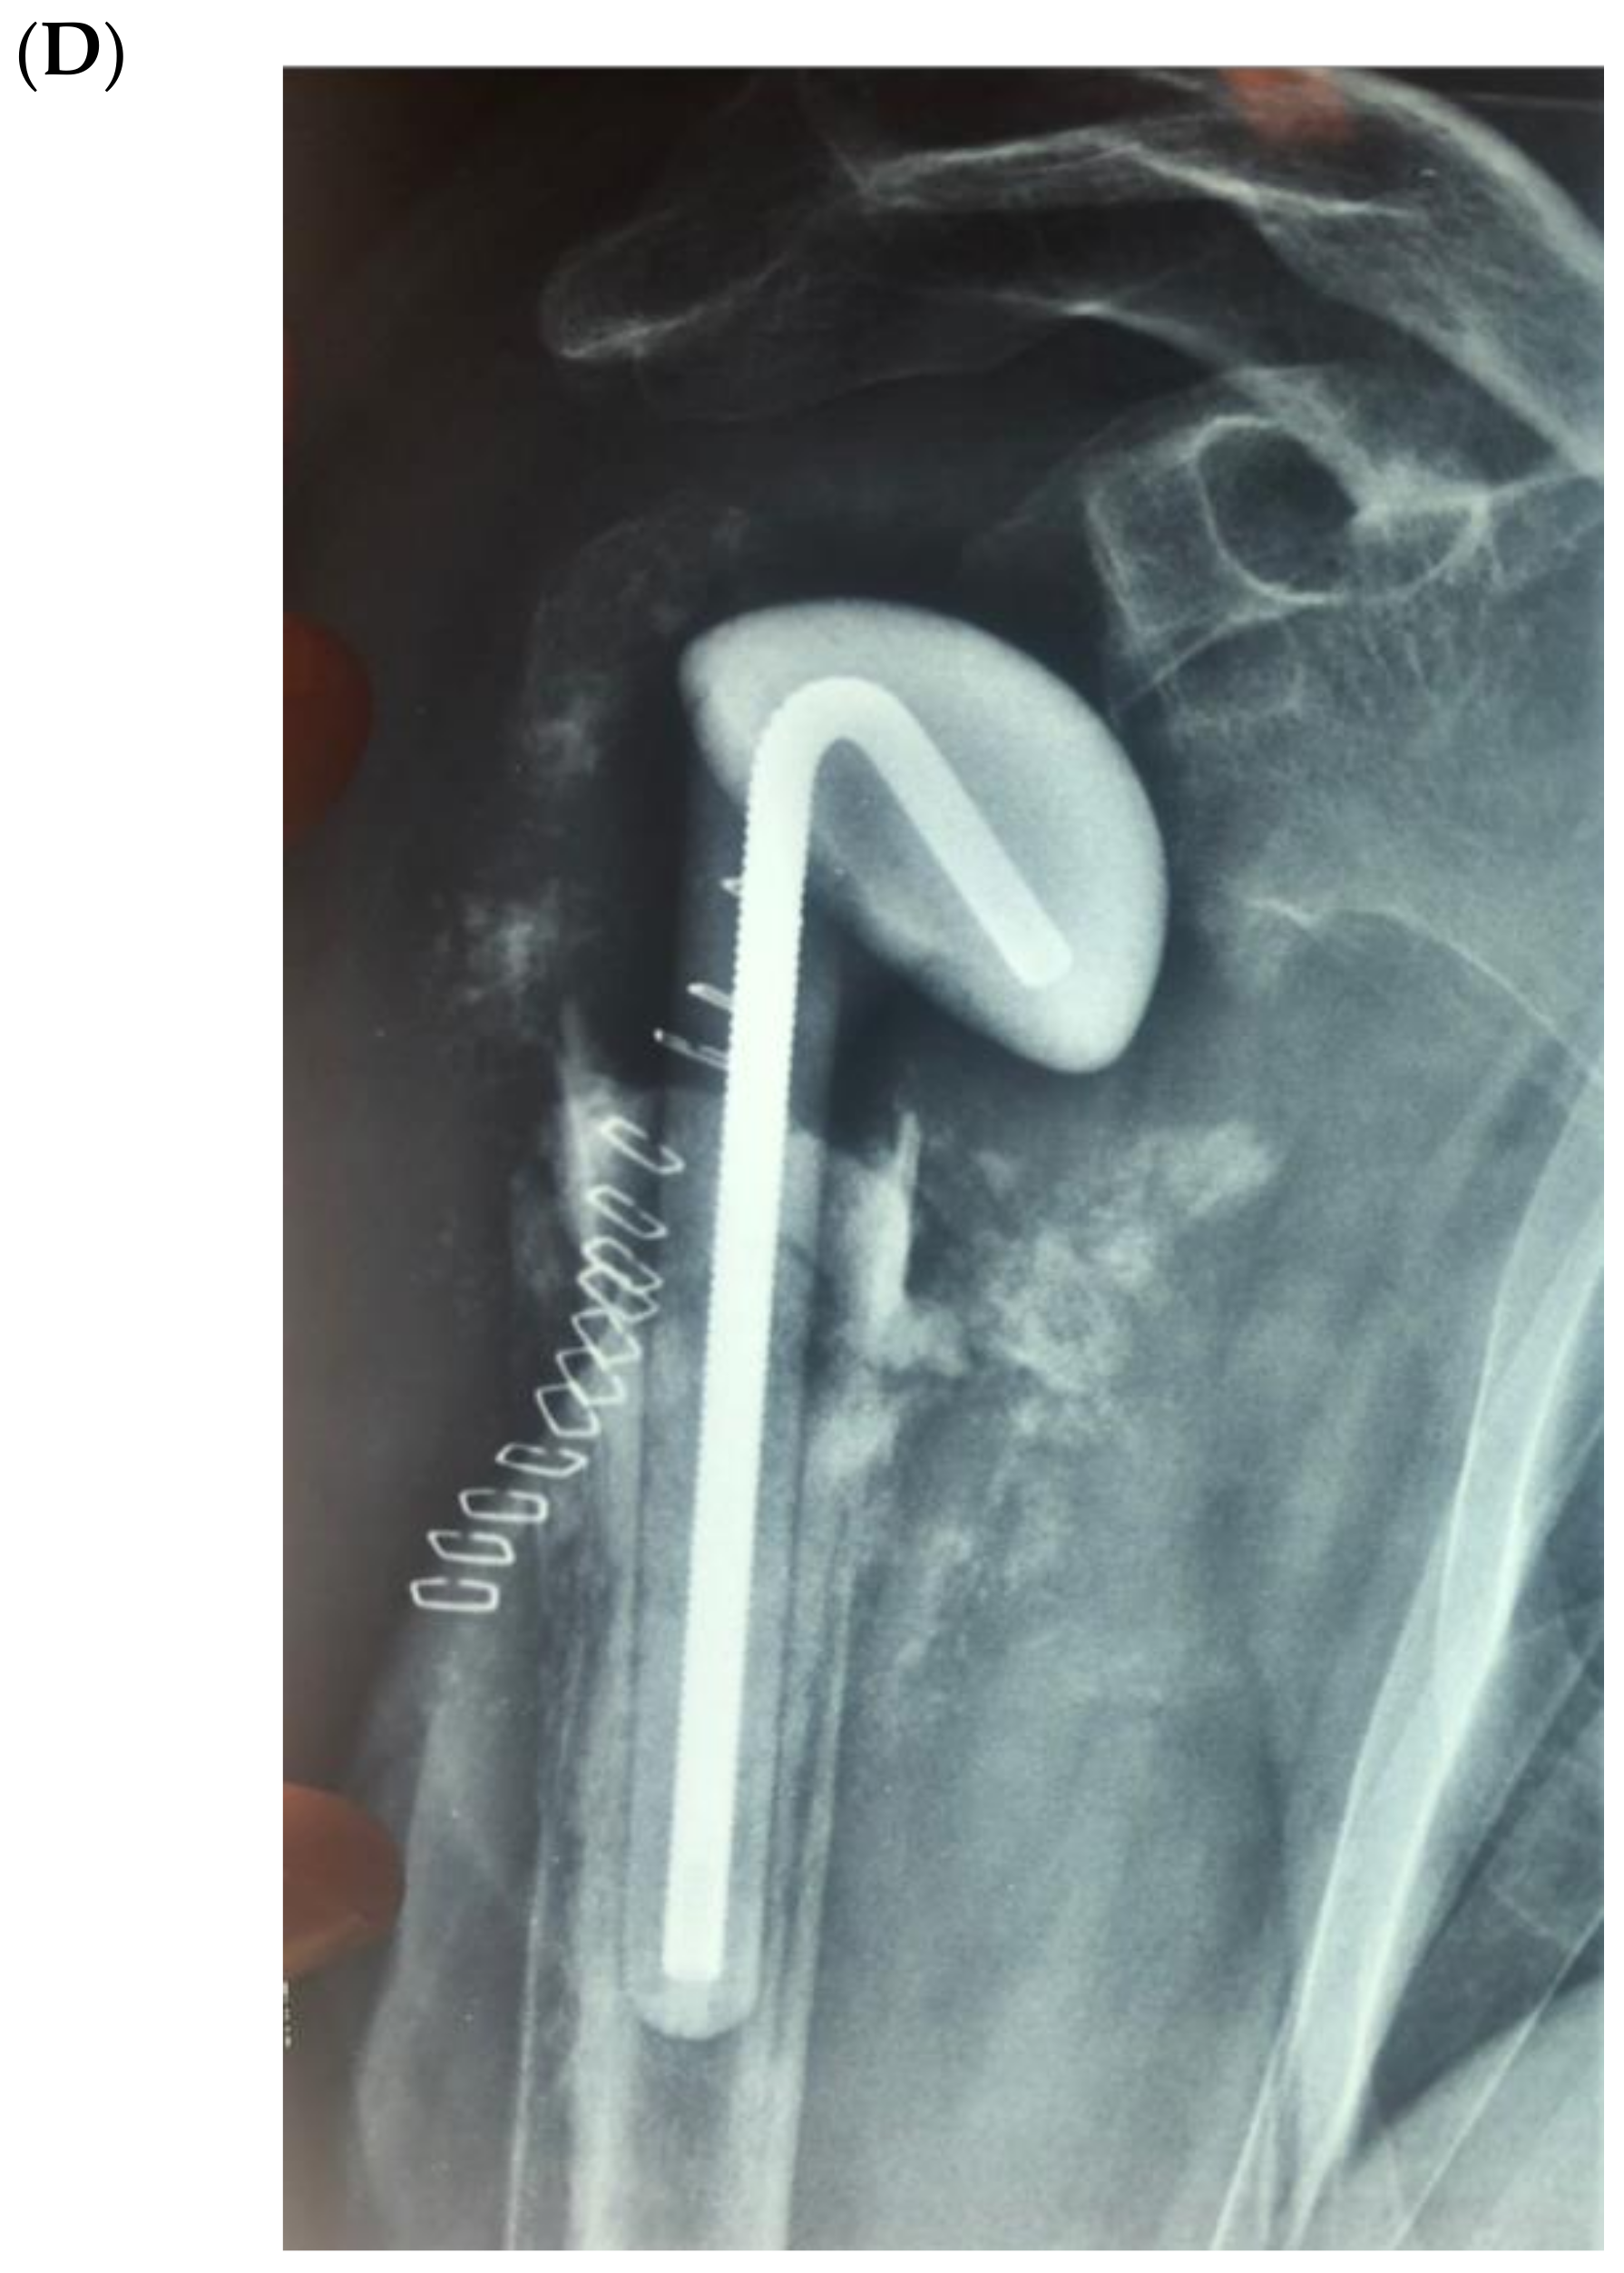

Figure 4 illustrates an infected case of proximal humerus fracture sequelae, originally treated with a plate, then treated according to our protocol. After plate removal, an RSA was implanted, which subsequently dislocated, resulting in infection. A two-stage procedure was performed: removal of the RSA, debridement, and implantation of a cement antibiotic spacer with vancomycin. MicroDTTect identified the pathogen (Cutibacterium acnes), intravenous antibiotics and infection eradication followed.

Figure 4.

(A) The X-ray of a case of an infected proximal humerus fracture sequelae, originally treated with a plate. (B) After plate removal, the first RSA was implanted, which subsequently dislocated, resulting in infection. (C) A two-stage procedure was performed: removal of the RSA, debridement and implant of a cement antibiotic spacer with vancomycin. (D) Spacer X-ray postoperative image.